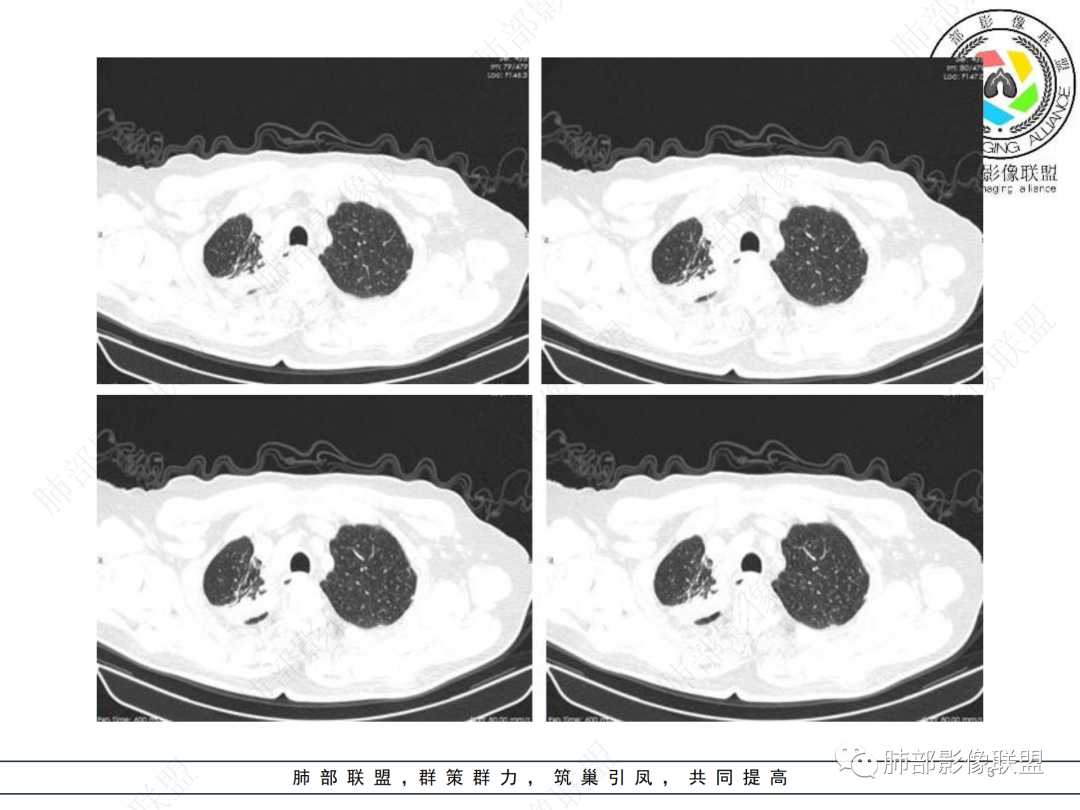

男性,69岁 反复咳嗽2年余,加重3天入院。CT示右肺上叶尖段不规则实变影,周边伴条索影,支气管未见明显堵塞,增强不均匀强化,考虑为恶性,腺癌可能

男,69,反复咳嗽2年,加重3天入院,右肺上叶软组织密度肿块影,边界尚清晰,边缘见毛刺及胸膜牵拉,右肺上叶支气管壁增厚,增强扫描不均匀性强化,考虑腺癌可能,鉴别炎性病变。

右侧胸廓变小,右肺上叶团块,边缘毛糙,长索条,周围斑点影,邻近胸膜增厚,气管不规整,密度不均,不均匀强化,考虑炎性肉芽肿,腺癌待排。